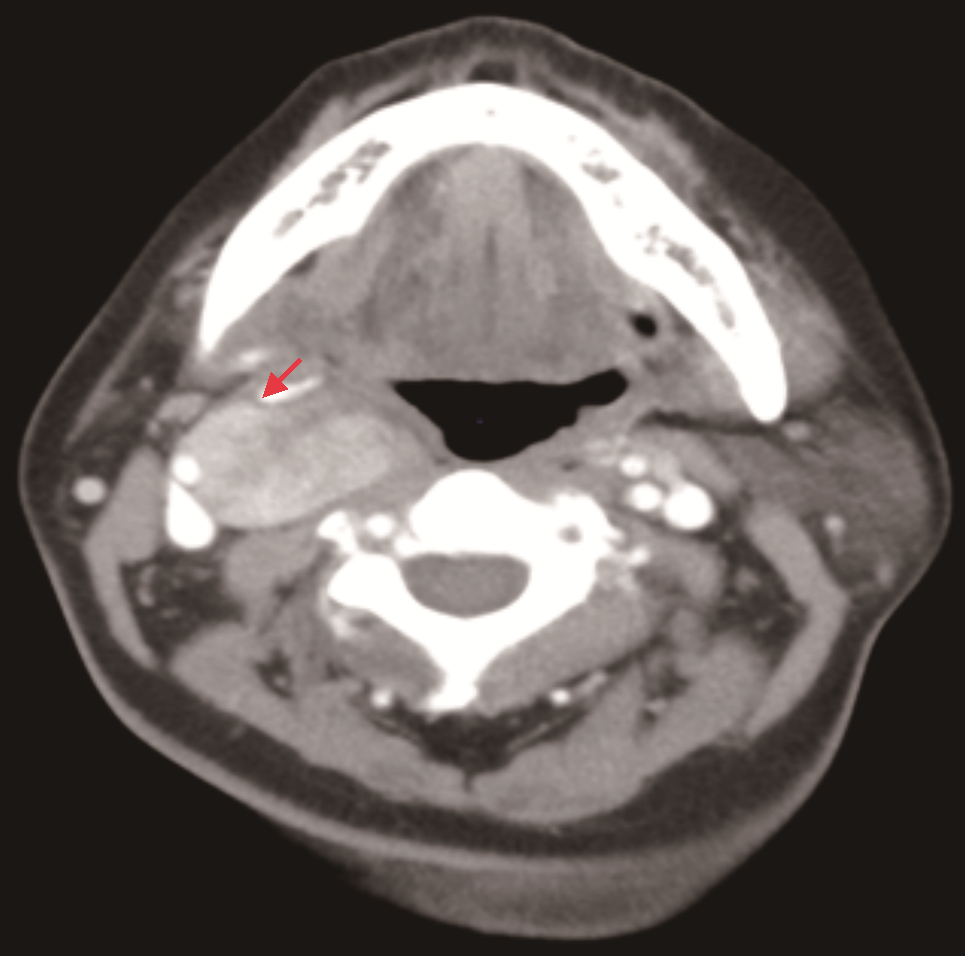

入院时查体:颈软,颈部可见5 cm横行瘢痕。右侧上颈部可及一肿物,约4 cm×3 cm,质地韧,表面光滑,可横向活动,纵向活动差未闻及杂音,未触及震颤。既往史:患者7年前因甲状腺肿物曾在外院行手术治疗,病理为结节性甲状腺肿,术后定期复查;患者高血压病史5年,自诉血压控制尚可。患者否认冠心病、糖尿病、心房黏液瘤和库欣综合征等病史。家族史:哥哥为甲状腺肿瘤患者。增强CT:右侧颈动脉鞘间隙可见一实性肿物(图1),形态欠规则,边界尚清,大小约3.5 cm×2.6 cm,增强扫描明显不均匀强化,颈内外动脉分离;提示右颈鞘肿物,倾向颈动脉体瘤。超声:甲状腺右残叶中部内侧见一个低回声结节,大小0.8 cm×0.7 cm,边界不清,左侧残叶上极内侧见一低回声结节,大小0.6 cm×0.3 cm,边界尚清;右侧中上颈颈鞘深面见一个实性肿物,大小约3.5 cm×3.5 cm(图2),向前推压至颈鞘,致颈内、外动脉夹角增大,形态欠规则,边界尚清。提示:甲状腺右叶残叶实性结节,炎性与癌待鉴别;甲状腺左叶残叶结节,良性;右颈中上颈实性肿物,良性,符合神经源肿瘤。心电图、胸部CT扫描及实验室检查未见明确异常。

患者发现颈部肿物半年并伴有典型霍纳综合征表现,体格检查肿物可横向活动,纵向活动差,未闻及杂音,未触及震颤。CT提示颈内外动脉分离,倾向颈动脉体瘤,但超声提示向前推压肿物至颈鞘,致颈内、外动脉夹角增大。综合患者病史及影像学表现,临床倾向于右上颈神经鞘瘤,来自交感神经。术前诊断:颈部神经鞘瘤,甲状腺结节(外院术后复发,不除外恶性),颈交感神经麻痹(霍纳综合征)。

MS肿瘤内含有大量黑色素颗粒,黑色素中的稳定自由基团在磁场中呈顺磁性,减少核磁中T1、T2的弛豫时间,表现出T1WI高信号,T2WI极低信号[10]。因此核磁(MRI)常常作为诊断MS的首选影像学检查,尤其是对于椎管内的MS。相比之下,CT对于椎管外MS可起到一定的诊断作用。遗憾的是,本例患者术前行CT和超声检查,综合诊断为神经鞘瘤,未行磁共振检查。我们认为,对于椎管外MS,术前高水平超声及多元化检查为MS的术前诊断可提供一定帮助,尤其是磁共振检查对术前诊断可起到极为重要的作用。

MS在影像学中由于邻近颈动脉窦和血管,术前常被误诊为颈动脉体瘤。其术中快速病理及术中所见常常引起临床医师对MS的关注。然而对于MS的诊断,术后免疫组化分析、网状蛋白染色以及与颈交感神经的相互关系至关重要。大多数MS病灶直径>5 cm,切面为柏油样黑色。镜下MS表现为梭形、上皮样细胞,胞质内可见含量不等的色素,其银染呈阳性,PAS染色呈阴性。MS免疫组化结果在不同报道中结果不尽相同,但多数S-100,HMB-45呈阳性[5,11]。但也有研究显示,MS和黑色素瘤都可能表达S-100或其他黑色素细胞标志物,网状蛋白染色在区分MS和黑色素瘤方面非常有效[7]。MS生物学行为具有恶性潜能,后续生物学行为往往难以估计,可发生术后局部复发、浸润周围组织及远处转移,但后两种较为罕见。目前为止,全球对于MS的报道不足200例,Torres-Mora等[12]对40例恶性MS患者进行了统计,发现局部复发率及疾病特异性死亡率分别为35%和27%,42%的患者发生远处转移,并且累及肺、肝、脑、骨。恶性MS的复发和转移较快,而非恶性MS复发时间大约为4~5年后。在以往的研究中,MS大多数临床上被认为良性肿瘤,但由于MS具有恶性潜能,因此对于MS的综合治疗以及随访仍然是不可忽视的。考虑到患者有复发和转移的倾向,许多学者认为MS应当被当作恶性肿瘤诊治[13]。但并不是所有的MS患者均接受术后放疗或辅助治疗,目前的个案报道也未详细描述术后治疗方案及术后生存时间。当局部浸润不能完全切除肿瘤时以及术后免疫组化提示分化较低且恶性潜能较高,建议辅助放疗,以防止局部复发和转移[14, 15, 16, 17]。本例患者免疫组化结果提示,S-100与Vimentin阳性,考虑为神经来源,但其余结果显示为阴性,且Ki-67<1%,与以往报道的免疫组化结果有一定的差异,因此我们认为,其MS恶性潜能较低,未给予术后辅助治疗,建议患者定期随访观察。